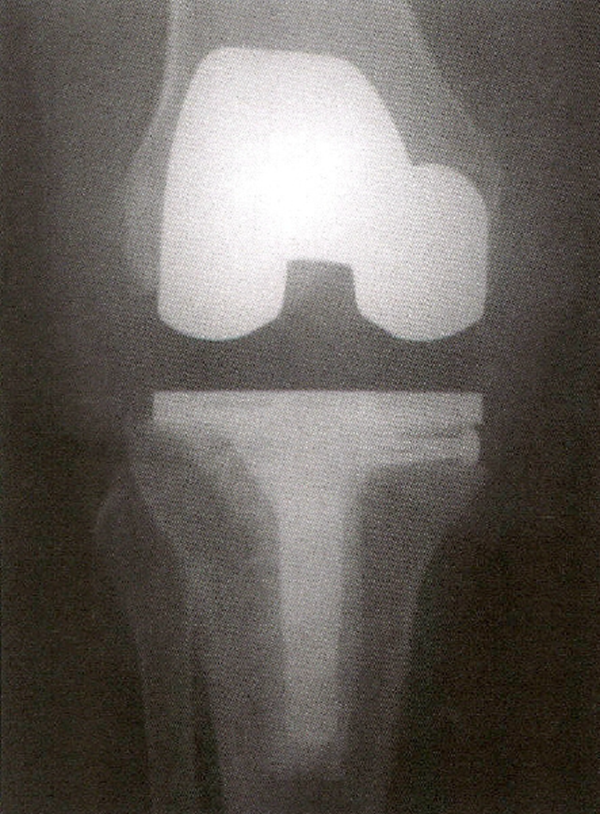

Brand等首先报道了使用与胫骨金属托相配合的金属楔形垫解决胫骨缺损的方法(图4)。经过平均3年的随访,22例膝关节无1例出现胫骨假体松动。大多数流行的膝假体采用组合式的楔形垫和块状垫片,它们可与股骨和胫骨假体相组合,用于治疗各种骨缺损。利用这些配件,手术医师可在术中根据1处或多处具体缺损为患者制订个性化假体。

图4 用于加强股骨和胫骨的组配式楔形模块